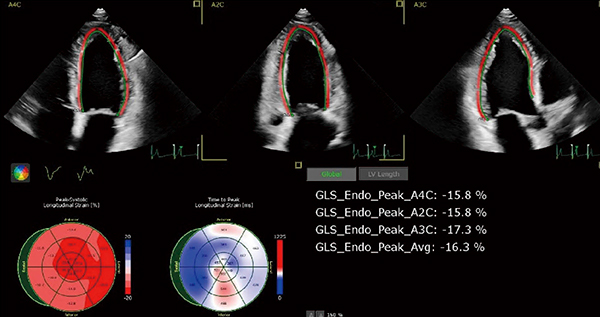

3.AutoStrain LV/LA/RV

スペックルトラッキング解析ソフトウエアである“AutoStrain”は,左室(図3),左房,右室の3種がリリースされており,それぞれのストレイン値を1ボタンで算出することができる。これを可能としたのは,下記2種類の自動化アルゴリズムである。

図3 AutoStrain LV

1ボタンでブルズアイ表示とともにGLSが算出される。

1)自動で断面を認識

AutoStrainでは,選択された画像の四腔像,二腔像,三腔像など,断層像の分類を自動で行う。6000例のデータに基づいて開発されたこのアルゴリズムは成功率99%を誇り,解析時間の大幅な短縮をもたらす。

2)自動でROIを設定

左室,左房,右室に特化したテンプレートを用いて自動でROIが設定される。装置が自動で設定したROIは,簡便に編集することもできる。

従来のスペックルトラッキング解析は,検者が各断面の画像を選択し,マニュアルでROIを設定するなど時間がかかっていたため,検査時間外で解析を行ったり,せっかく解析をしても再現性が低いなどの問題があった。AutoStrainは,解析時間を短縮し,かつ装置上で解析できるので,ルーチン検査内でスペックルトラッキング解析を取り入れることを実現する。